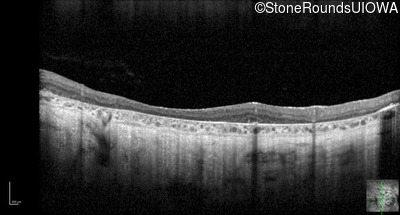

Optical Coherence Tomography - Left - 10/225

Exemplar / OCT Stack